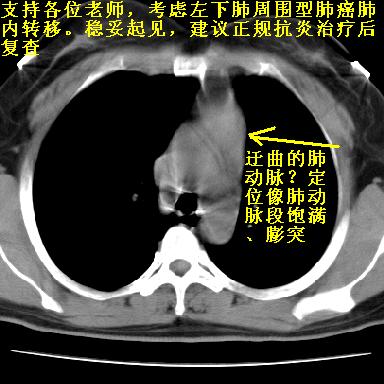

患者毕竟年轻,结论还应慎重.

支持。另外,双侧腋下似见增大淋巴结影,有侧乳腺4、5点处皮下高密度结节影是什么?食管中下段有没有问题?病人比较年轻,因此诊断恶性肿瘤要慎重,多结合临床和其他检查,多考虑一些,也可短期抗炎治疗后复查。

右肺多发小结节影,边界清楚,符合转移瘤的特点;2、左下肺偏心性空洞影,右侧乳腺内高密度影,需要查体除外右侧乳腺肿瘤;3、腋窝淋巴结肿大,考虑转移。